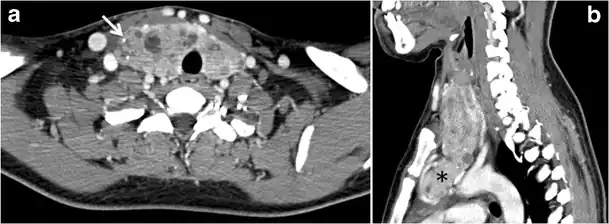

Fig. 1. An incidentally discovered colloid nodule with calcification, shown on CT scan of a 58-year-old female patient. a Non-enhanced axial CT scan of the neck demonstrates a coarse calcification at the left thyroid inferior pole. b Sagittal grey scale ultrasound of the thyroid demonstrates a heterogeneous nodule with a predominant cystic component. Calcification was not seen in the ultrasound, probably due to its lower location in the superior mediastinum.[1]

Fig. 2. A 51-year-old female patient post left hemithyroidectomy, with incidentally discovered a right thyroid colloid nodule on CT scan. an Enhanced axial CT scan of the neck demonstrates a well-defined, hypodense right thyroid nodule (white arrow) with no internal calcifications or cervical lymphadenopathy. b Transverse greyscale thyroid ultrasound demonstrates a well-defined, hypoechoic right thyroid lobe nodule with a central echogenicity including comet tail (ring down) artefacts (white arrow). No vascularity (not shown) or calcifications were detected.